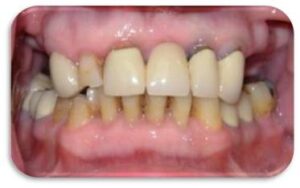

Η Προσθετικη οδοντιατρικη ειναι ο κλαδος της οδοντιατρικης που ασχολειται με την αποκατασταση μεγαλης η μικρης νωδοτητας στον οδοντικο φραγμο.

Η Προσθετικη Οδοντιατρικη χωριζεται σε

- Ακινητη προσθετικη, δηλαδη στεφανες και γεφυρες

- Κινητη προσθετικη, δηλαδη μερικες και ολικες οδοντοστοιχιες

- Προσθετικη επι εμφυτευματων